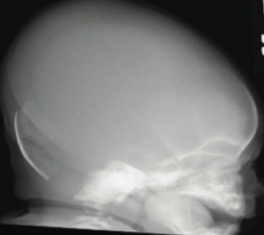

Muhammad Ubaidulhaq, MD; Alyssa Bottrell, MS; Safwan Riaz, MD

A 1-day-old girl born to a 24-year-old gravida 2, para 1 mother at almost 37 weeks’ gestation was referred to our facility with concern regarding a soft skull.